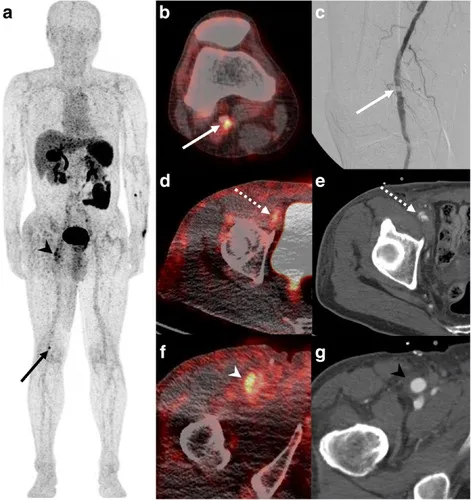

BJR publishes special feature on imaging patients with stable chest pain. BJR, the international research journal of the British Institute of Radiology, has published a collection of articles on the theme of imaging patients with stable chest pain, guest-edited by leading experts Professor Matthijs Oudkerk & Professor Edwin van Beek. Millions of people around the world suffer from chest pain. Diagnosing the cause of chest pain & identifying the level of risk are integral to the prevention of serious coronary events & poor patient outcomes. Imaging is central to these efforts & provides vital information to primary care physicians, cardiologists & the variety of doctors who manage patients with stable chest pain. Following the publication of the SCOT-HEART trial in 2015 (a study to see if coronary artery calcium score & computed tomography coronary angiogram alters the proportion of patients diagnosed with angina due to coronary heart disease), a new era of non-invasive coronary imaging has opened up. This BJR special feature covers many of the important topics & questions facing the scientists & clinicians working in the field & presents a collection of insightful Review articles & Commentaries from leading international experts. Professor Edwin van Beek said “This special feature is essential reading for any medical professionals interested in stable chest pain. The articles cover vital topics such as vulnerable plaque, cost-effectiveness for imaging stable ischemic disease, the potential for functional coronary & cardiac CT imaging, the role of machine learning, the role of MRI for the assessment of chest pain & the role of imaging in the evaluation of heart valve disease”. Professor Matthijs Oudkerk explains “This special feature marks the moment of publication of the first hard evidence that non-invasive coronary CT imaging in patients with chest pain saves lives compared to current medical practice & at the same time is a lot less harmful for the patient, costs less & is more effective. This special feature is not to be missed!”. You can access the special feature, here. Image Figure 1 from \"MRI perfusion in patients with stable chest-pain\" Images Figure 1 from "MRI perfusion in patients with stable chest-pain" Figure 1. The top row is an example of an ischemic perfusion defect, where the stress perfusion image shows a clear hypoperfused area (red arrows), whereas the LGE image shows no defect. The bottom row shows an infarct-related perfusion defect, where on both, stress perfusion (slightly hypoenhanced tissue, red arrows) and LGE image (strongly hyperenhanced tissue) a defect is shown (red arrows). This example of an infarct patient also demonstrates the superiority of LGE to delineate scar in comparison to the perfusion approach. In scar, the extracellular Gd-chelate contrast medium distributes in a large extracellular (fibrotic) compartment during first-pass, which increases the signal in the fibrotic tissue explaining its reduced sensitivity to detect hypoperfusion in scar. This reduced sensitivity to detect hypoperfusion is not observed in viable myocardium (with small extracellular compartment). LGE, late gadolinium enhancement. Image Figure 4 from \"Non-invasive imaging of high-risk coronary plaque: the role of computed tomography & positron emission tomography\" Figure 4 from "Non-invasive imaging of high-risk coronary plaque: the role of computed tomography & positron emission tomography" Figure 4. 18F-GP1 arterial uptake in right popliteal artery. 18F-GP1 PET-CT images of a patient who had recently undergone right common femoral artery endarterectomy & right popliteal artery angioplasty. Anterior maximum intensity projection & axial images taken 120 min after 18F-GP1 injection show focal increased uptake in the right popliteal artery (a, b); arrows), which corresponds to a thrombotic lesion after angioplasty (c). Additional 18F-GP1 uptake is seen in the dissected right distal external iliac artery (d, e); dotted arrows) & right common femoral artery (a, f); arrow heads) where endarterectomy was performed 3 days prior to the PET-CT (g, arrow head). Images courtesy of Chae et al.40 PET, positron emission tomography. Image Figure 5 from \"Vulnerable plaque imaging using 18F-sodium fluoride positron emission tomography\". Figure 5 from "Vulnerable plaque imaging using 18F-sodium fluoride positron emission tomography" Figure 5. Examples of coronary plaques with significant uptake on 3 h PET & low tracer activity of 1 h post injection imaging. Short axis images of proximal left anterior descending, proximal circumflex (A) & distal right coronary artery (B) plaques (arrows) which had a TBR <1.0 on 1 h PET (left column) & showed uptake exceeding the 1.25 TBR threshold at 3 h. This research was originally published in JNM. Kwiecinski J, Berman DS, Lee SE, Dey D, Cadet S, Lassen ML, Germano G, Jansen MA, Dweck MR, Newby DE, Chang HJ, Yun M, Slomka PJ. Three-Hour Delayed Imaging Improves Assessment of Coronary 18F-Sodium Fluoride PET. J Nucl Med. 2019 Apr;6025 :530–535. doi: 10.2967/jnumed.118.217885. PET, positron emission tomography; SUV, standardized uptake value; TBR, target to background ratio. Related links British Institute of Radiology British Journal of Radiology British Journal of Radiology special feature Professor Edwin van Beek Professor David Newby Professor Marc Dweck SCOT-HEART What is a CT scan? What is a PET scan? What is a MR scan? What is a PET-CT scan? "MRI perfusion in patients with stable chest-pain" "Non-invasive imaging of high-risk coronary plaque: the role of computed tomography & positron emission tomography" "Vulnerable plaque imaging using 18F-sodium fluoride positron emission tomography" Social media tags & titles BJR publishes special feature on imaging patients with stable chest pain. @BIR_News @BJR_Radiology @SINAPSECENTRE @MarcDweck #ChestPain Publication date 16 Sep, 2020